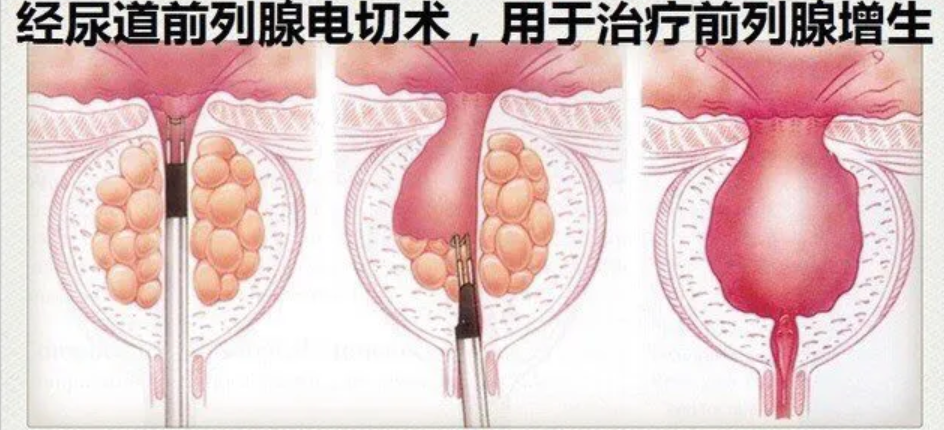

鉴于保守治疗效果有限,张大爷与家属决定接受手术治疗。泌尿外科团队为他制定了详细的治疗方案,并进行了等离子前列腺电切微创手术。

前列腺是男性特有的腺体,随着年龄增长,尤其在中老年阶段,前列腺组织会逐渐增生肥大。当前列腺体积增大时,会压迫穿行其中的尿道,从而引起一系列排尿症状。患者常感到排尿费力、尿流变细、射程变短,有时排尿后仍有滴沥,出现尿频、尿急,尤其是夜尿次数增多。如果梗阻加重,膀胱内残余尿增多,可能引起反复尿路感染,甚至影响肾脏功能。